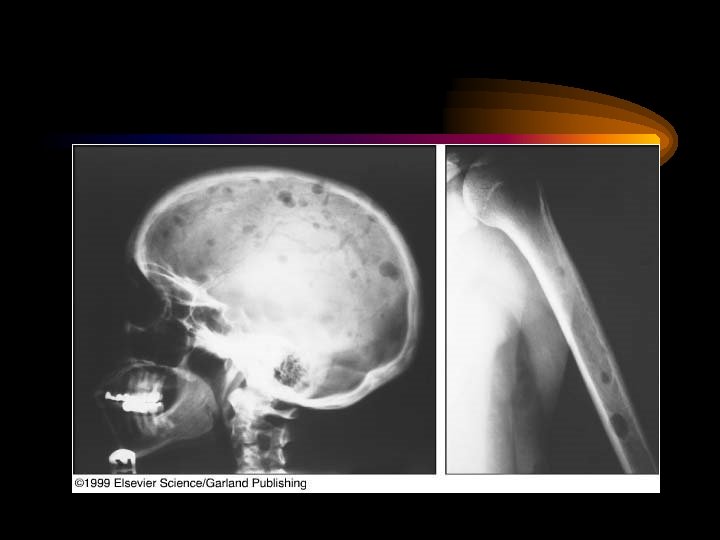

Bone Disease • Lytic Lesions – 60% • Osteoporosis, Fx, Compression Fx – 20% • Myeloma Cells Produce Cytokines that: – Stimulate Osteoclastic Activity – Inhibit Osteoblastic Activity • Can be Detected by Plain Xray

Lytic lesions(Punched out lesions) on X Ray.

Multiple myeloma: multiple lesions in skull – Lab 11